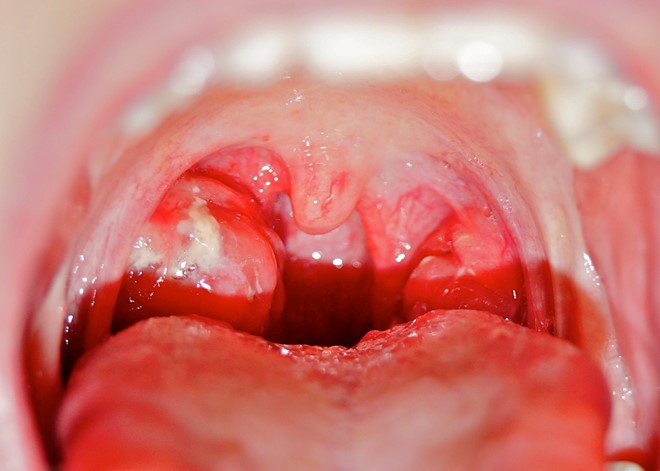

| Viêm họng có thể gây ra một số biến chứng như viêm cầu thận cấp, thấp tim, viêm khớp cấp. Ảnh: Seoarticlelibrary . |